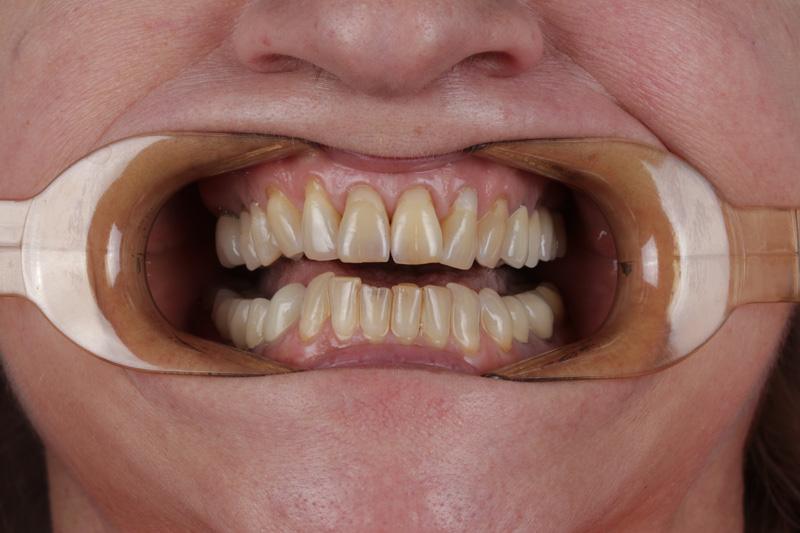

Pomimo zaleceń dr do wdrożenia również leczenia ortodontycznego, Pacjentka, znając wszystkie wady i zalety bezwzględnie zdecydowana zakamuflować stłoczenia, nieprawidłowości kontaktów, płaszczyzny zgryzowe, tylko i wyłącznie protetycznymi rozwiązaniami. Dr Joanna ustaliła z Pacjentką pod Jej wymagania wspólny plan działań. Wybierając takie rozwiązanie lekarz i laboratorium ma zawsze utrudnienie, by jaknajbardziej harmonijnie zaplanować projekt uśmiechu.

Pacjentka, zgłaszając się już na kolejną wizytę świadomie podjęła opcję pośrednią z proponowanych działań: wyleczenie zębów zachowawczo, endodontycznie z zabezpieczeniem protetycznym, estetyczne korekty uśmiechu licówkami, ćwierćkoronami i koronami, jednak bez pełnej przebudowy zwarcia (z zachowaniem starszych odbudów w strefach bocznych, które były wykonane na implantach w przeszłości), która jest zawsze najbardziej polecana, odtwarza prawidłowe kontakty, a także umożliwia lekarzowi i technikowi najlepsze warunki do nadania odpowiednich i harmonijnych kształtów. Te wszystkie działania chronią na przyszłość staw skroniowo-żuchwowy.